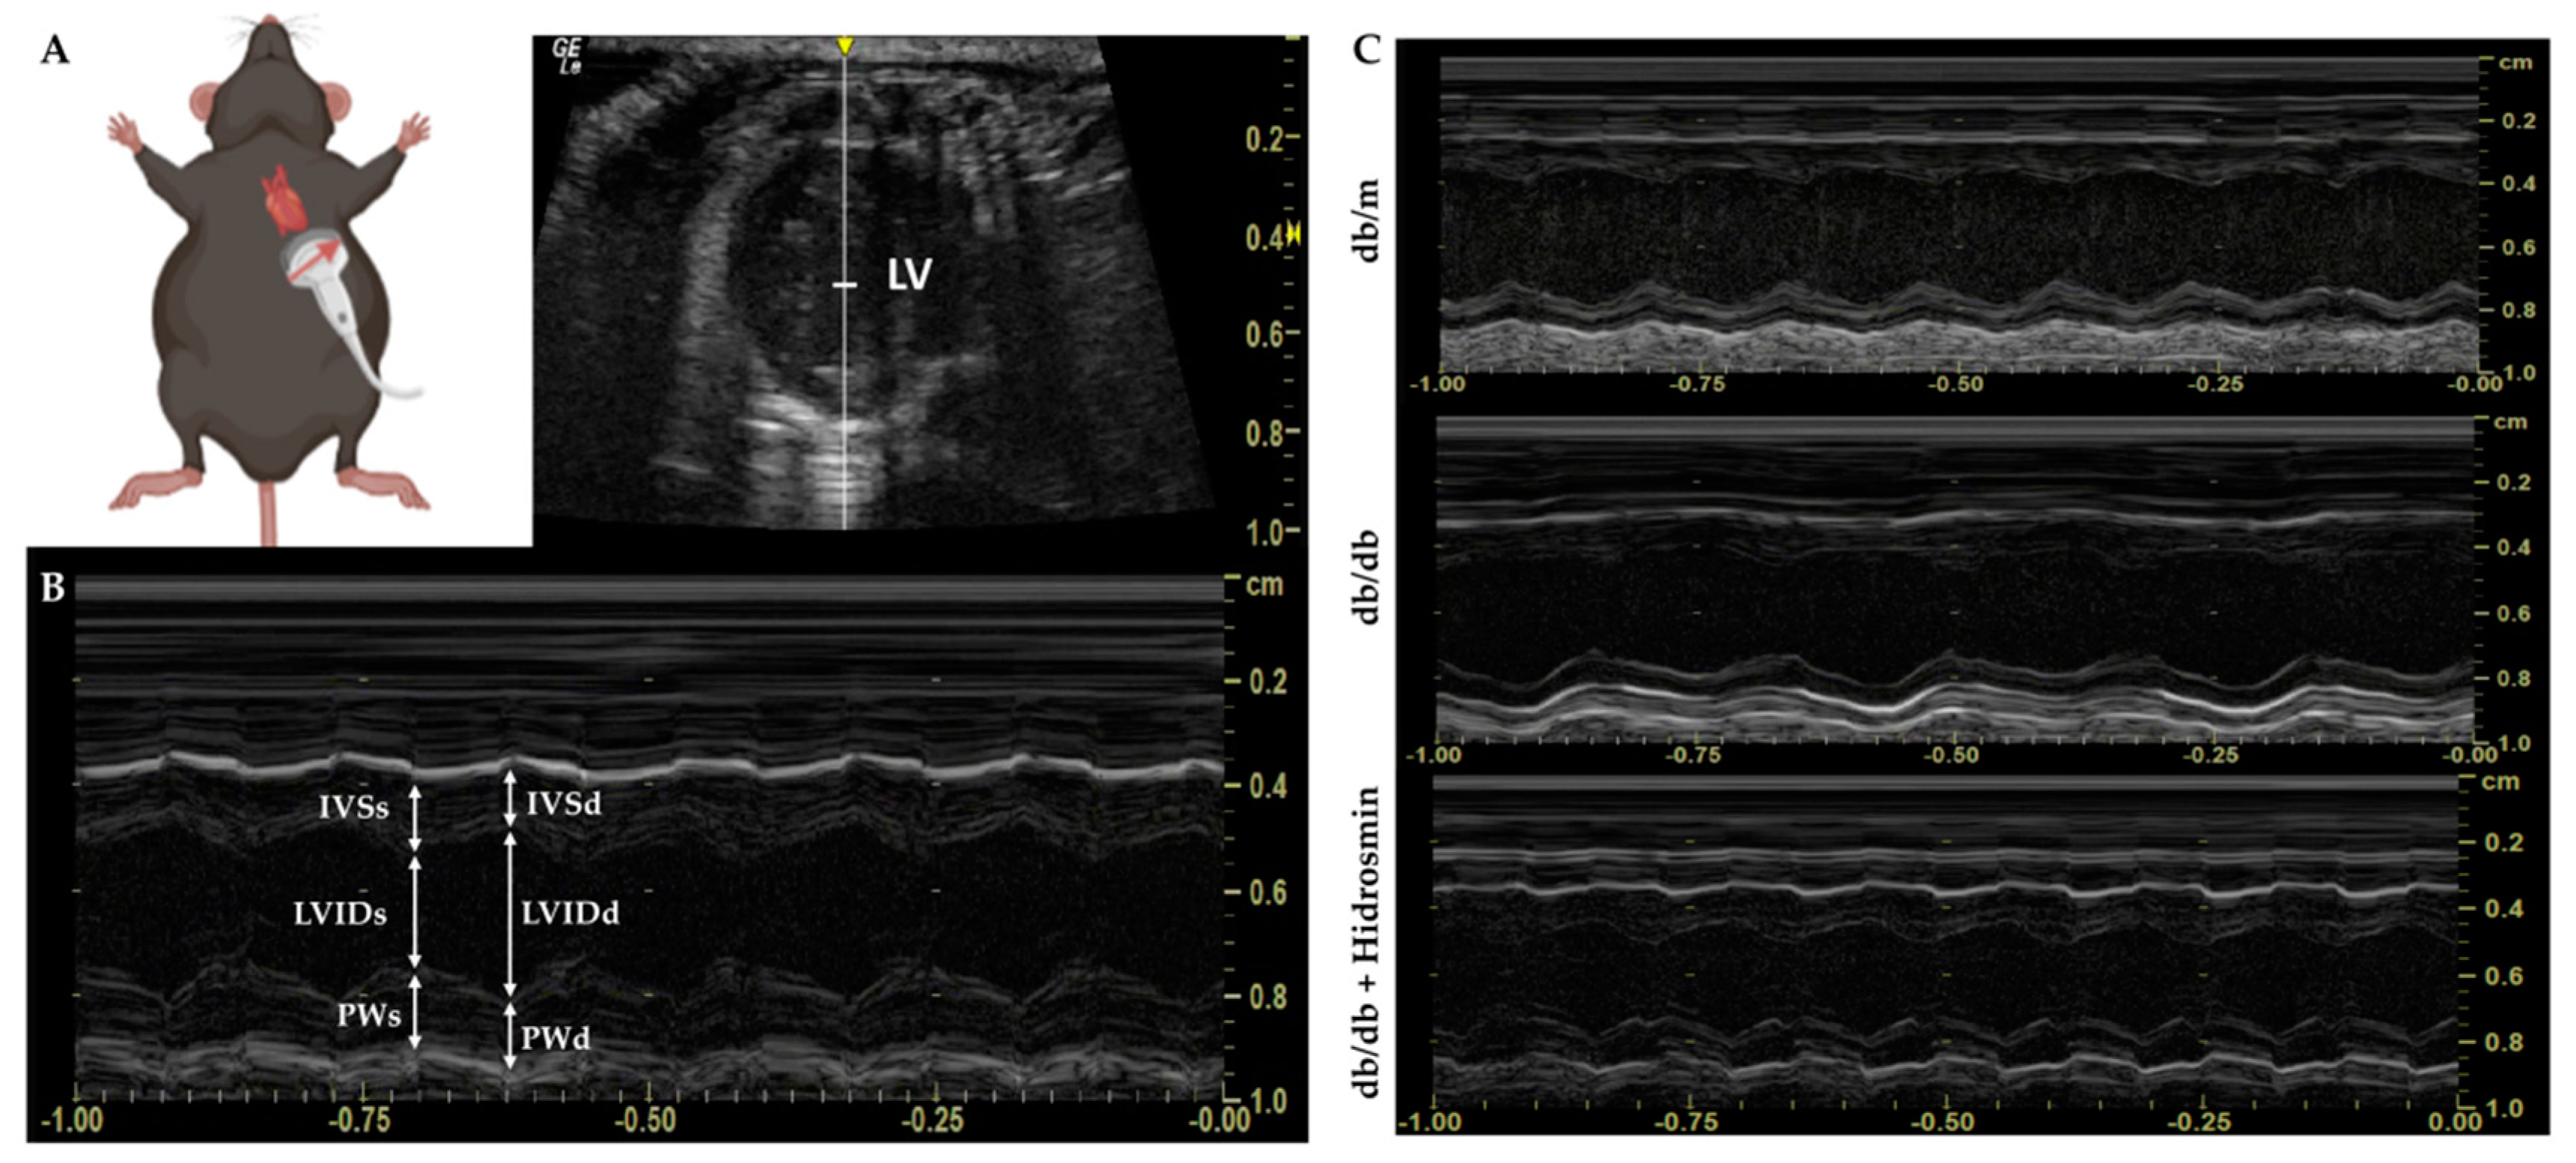

2.8. Echocardiography Assessment

3.5. Hidrosmin Treatment Does Not Affect the Structure and Function of Hearts from Diabetic Mice

| Variables | db/m | db/db | db/db + H |

|---|---|---|---|

| IVSd (μm) | 102.4 ±4.3 | 115.4 ± 15.2 | 109.6 ± 15.1 |

| LVIDd (μm) | 379.5 ± 4.8 | 336.2 ± 46.6 | 336.3 ± 37.1 |

| PWd (μm) | 99.0 ± 2.4 | 106.2 ± 12.9 | 94.2 ± 11.8 |

| IVSs (μm) | 144.8 ± 2.7 | 171.9 ±18.9 | 165.8 ± 18.0 |

| LVIDs (μm) | 260.0 ± 4.5 | 222.4 ± 36.7 | 219.2 ± 25.3 |

| PWs (μm) | 138.6 ±2.4 | 137.1 ± 13.9 | 120.4 ± 16.9 |

| LV mass (μg) | 148.6 ± 4.7 | 146.4 ± 19.5 | 125.3 ± 16.6 |

| LV mass/BW (μg/g) | 5.0 ± 0.2 | 2.6 ± 0.4 * | 2.4 ± 0.3 * |

| EF (%) | 67.1 ± 2.4 | 71.2 ± 9.9 | 72.1 ± 10.2 |

| FS (%) | 31.3 ± 1.6 | 34.2 ± 5.0 | 35.4 ± 5.4 |

| PWT (%) | 40.5 ± 5.1 | 28.8 ± 7.4 | 29.2 ± 8.3 |